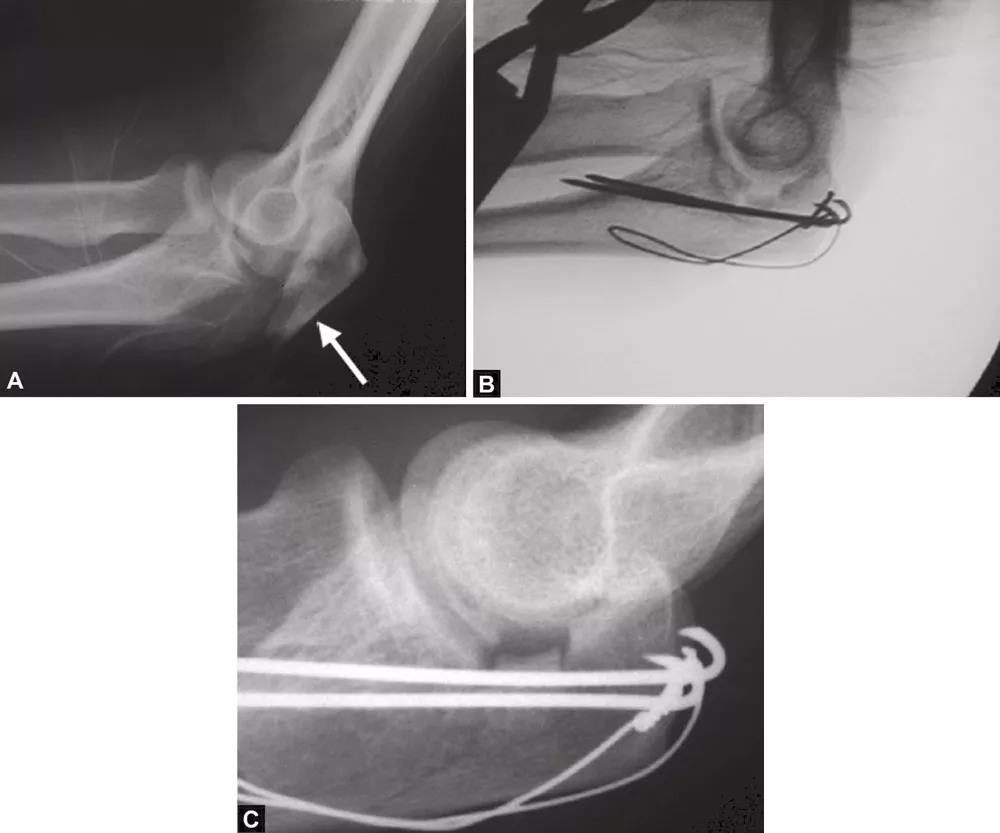

当存在鹰嘴关节面部分压缩时,必须将其对应肱骨滑车抬高复位。在三头肌止点用钢丝牵开鹰嘴尖端(图4),复位压缩骨折,用细克氏针将其推靠在肱骨滑车上维持位置。克氏针必须紧贴压缩骨折部位的软骨下骨来维持位置。此时,用高质量的侧位X线片检查来确定压缩骨折的复位,克氏针的位置是否良好是非常必要的。另一种方法是采用松质骨植骨来支撑复位的压缩骨折。

图4A和B(1)将鹰嘴拉下复位关节内松动的骨片,用横向箭头所示细克氏针,将其推挤在滑车上维持复位;(2)钢丝环穿过三头肌止点周围将鹰嘴拉下;(3)克氏针紧贴软骨下骨插入支撑松动的关节内骨片(给向箭头所示克氏针)